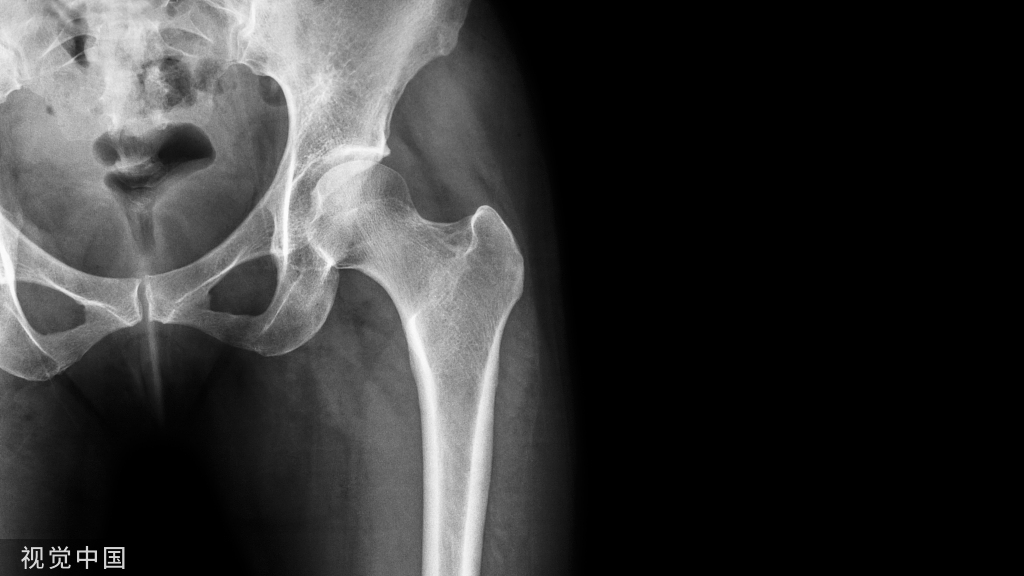

骨质疏松症( osteoporosis,OP) 是最常见的骨骼疾病,是一种以骨量低,骨组织微结构损坏,导致骨脆性增加,易发生骨折为特征的全身性骨病。

①脆性骨折: 是骨强度下降的最终体现,髋部和椎体脆性骨折是骨质疏松症的重要临床表现。